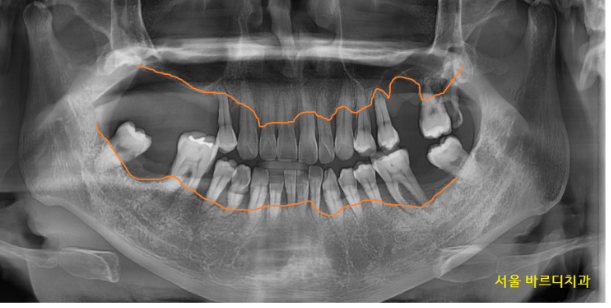

230327

윗니는 개수로만 4개 없음

아랫니는 2개 없음

앞으로 뽑아야하는 치아들

그래서 그런가 입안 상태도 좋지 못했습니다.

정상적인 치아가 없을정도였죠.

안 흔들리는 치아가 없었습니다.